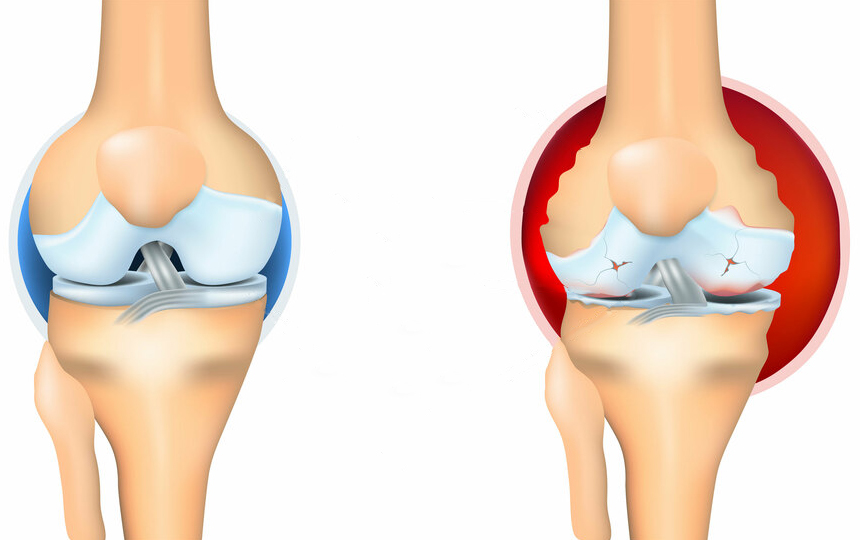

พวกนี้ไม่ช่วยเสริมสร้างข้อต่อหรือกระดูกอ่อนเลย พวกมันเพียงแค่ลดอาการชั่วคราว เช่น ปวด บวม อักเสบ ลองนึกดูว่าร่างกายจะเป็นอย่างไร เมื่อคนเรากินยา ทายาชา หรือฉีดยา ความเจ็บปวดก็จะหายไปชั่วคราว แต่เมื่อยาฤทธิ์หมด ความเจ็บปวดก็จะกลับมาอีก

อาการปวดเป็นสัญญาณสำคัญที่บ่งชี้ว่ามีความผิดปกติในข้อ การแค่ทำให้หายปวดจะทำให้สภาพของข้อต่อแย่ลง กระบวนการเสื่อมสภาพจะเร็วขึ้น 3-5 เท่า ส่งผลให้เกิดการเปลี่ยนแปลงที่ย้อนกลับไม่ได้ สูญเสียการเคลื่อนไหวและนำไปสู่การพิการในที่สุด

เมื่อเกลือเหล่านี้เกาะอยู่บนพื้นผิวของข้อต่อ คราบเกลือเหล่านี้เหมือนกระดาษทรายที่ทำลายเนื้อเยื่อรอบโดยรอบ กระดูก และกระดูกอ่อน เมื่อผลึกโตขึ้น เกลือจะเริ่มทำลายเนื้อเยื่อของกล้ามเนื้อ เอ็น หลอดเลือด และเส้นเลือดฝอย ทำให้เกิดการอักเสบ ติดเชื้อ บวม ก่อให้เกิดการอักเสบและปวดอย่างรุนแรง

นี่คือสาเหตุที่แพทย์ญี่ปุ่นเน้นการฟื้นฟูการไหลเวียนเลือดในข้อ เพื่อละลายเกลือที่สะสมมาหลายปี เปิดทางให้ของเหลวไขข้อหมุนเวียนได้ตามปกติ ซึ่งจะช่วยให้กระดูกอ่อนเริ่มฟื้นตัวตามธรรมชาติ

ในความเป็นจริงแล้ว ข้อต่อมนุษย์มีความสามารถในการฟื้นฟูตัวเองสูงมาก ข้อต่อเหล่านี้สามารถฟื้นฟูตัวเองได้เช่นเดียวกับหางของกิ้งก่า เพียงแค่ต้องได้รับความช่วยเหลือเล็กน้อย แค่ต้องเอาเกลือที่เกาะอยู่ออก แล้วกระบวนการฟื้นฟูก็จะเริ่มขึ้น